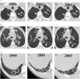

Central bronchiectasis

Bronchiectasis is a disease in which there is permanent enlargement of parts of the airways of the lung. Symptoms typically include a chronic cough with mucus production. [Source: Wikipedia ]